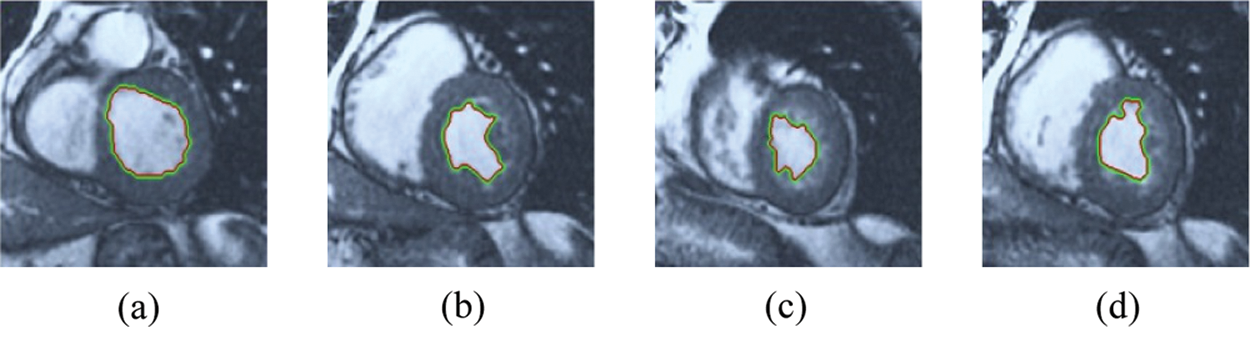

The BRW, HSRW, and ERW medical imaging segmentation schemes are executed on MATLAB, and examined on a short-axis of 3D multi-slices CMRI dataset [27]. Several segmentation performance metrics are utilized such as Dice Metric (DM), the Haussdorff distance (HS), and the Peak signal to noise ratio (PSNR). The BRW, HSRW, and ERW segmentation schemes are executed on a short-axis of 3D multi-slices CMRI datasets. The same multilayer CMRI dataset is segmented using various random walk methods. The presented results were obtained through using BRW, HSRW and ERW methods on five different groups of patients; each group contains 25 subject of multilayer CMR dataset. Experimental results illustrate that the BRW method can achieve a good segmentation of the LV cavity. The results of the HSRW algorithm have very comparable similarities to BRW, but with a slightly less efficiency and a much higher execution rate. Pre-calculations reduce the performance online time in offline mode. The average time of HSRW equals to 0.09 seconds for each slide. Raising the rate of K will improve the comparison and makes the process of segmentation more precise, but also reduces the execution time. The ERW technique results illustrate that this method has the greatest efficiency of segmentation. Figs. 5 to 7 show the resulting images of the BRW segmentation method on five sets of sample data. HSRW with pre-calculation segmentation method is applied on the same sets of sample data and illustrated in Figs. 8 to 10. Figs. 11–13 show the high efficiency segmentation using the ERW method with an earlier model for the same sets of sample data. The results of the Random Walk segmentation overcame the potential restrictions of the prior art CMR methods. The performance of segmentation is fast compared to segmentation methods based on edge and region. BRW precedes into account the properties of regions and edges, as shown in Figs. 5–7. Looking at the image as a graph, the technique makes it possible to integrate pixel relations with neighboring pixels. As a result, segmentation produces good quality BRW technique sections when their qualitative accuracy is compared to the ground truth, and this is also evident from the Tab. 1 measurements in the diastolic and systolic phases in Tab. 2 as well as in the complete cardiac cycle noticed. Figs. 8–10 illustrate the HSRW results. There are no dissimilarities observed in furthermost cases of CMR slides in the figures, but the correspondence measurements of the DM, PSNR and HS coefficients present that the results of the HSRW technique are worse than those of the BRW method. This presents that HSRW is an effective estimation of the random walk influence as mentioned in Tab. 1 and throughout the cardiac cycle in Tab. 2. The values of PSNR and DM are lower, whereas HS is higher than the BRW method, but with slight dissimilarities between HSRW and BRW methods throughout the blood circulation. The impact of execution eigenvectors pre-calculations is perfect when the execution time is faster than the BRW method and, in fact, more efficient than other segmentation method for LV heart segmentation. With the identical dataset, the ERW method shows a significant enhancement in efficiency, as presented in Figs. 11–13. From the scores, we can see that the segmentation is smoother and cleaner. The ERW method considers boundaries and areas, such as BRW, using the relations between adjacent pixels in the image. It also considers the additional regional advantage by including the assumptions that affect the results of the segmentation. Mean segmentation quality measurements are computed from the segmented images using correspondence measurements for instance DM, HS, and PSNR and verified for each method in the diastolic and systolic stages as presented in Tab. 1. Based on results, it can be determined that methods of random walk are enhanced in diastolic diagnosis and that their outcomes in the systolic stage are also of good efficiency. The results of the random walk segmentation methods in the complete blood circulation are shown in Tab. 2. The cardiac cycle similarity amounts indicate that DM and PSNR capacities of ERW are improved than the corresponding capacities in the case of the HSRW and BRW approaches; however, the HS measurements are lower than the equivalent measurements, as illustrated in Tab. 2. This designates that the ERW technique is the furthermost accurate segmentation technique among all the approaches stated above. The ERW technique has the uppermost value of PSNR, and the HSRW method has the lowermost value that denotes the uppermost speed in segmentation process.

Figure 11: ERW results for the first samples set

Figure 12: ERW results for the second samples set

Figure 13: ERW results for the third samples set